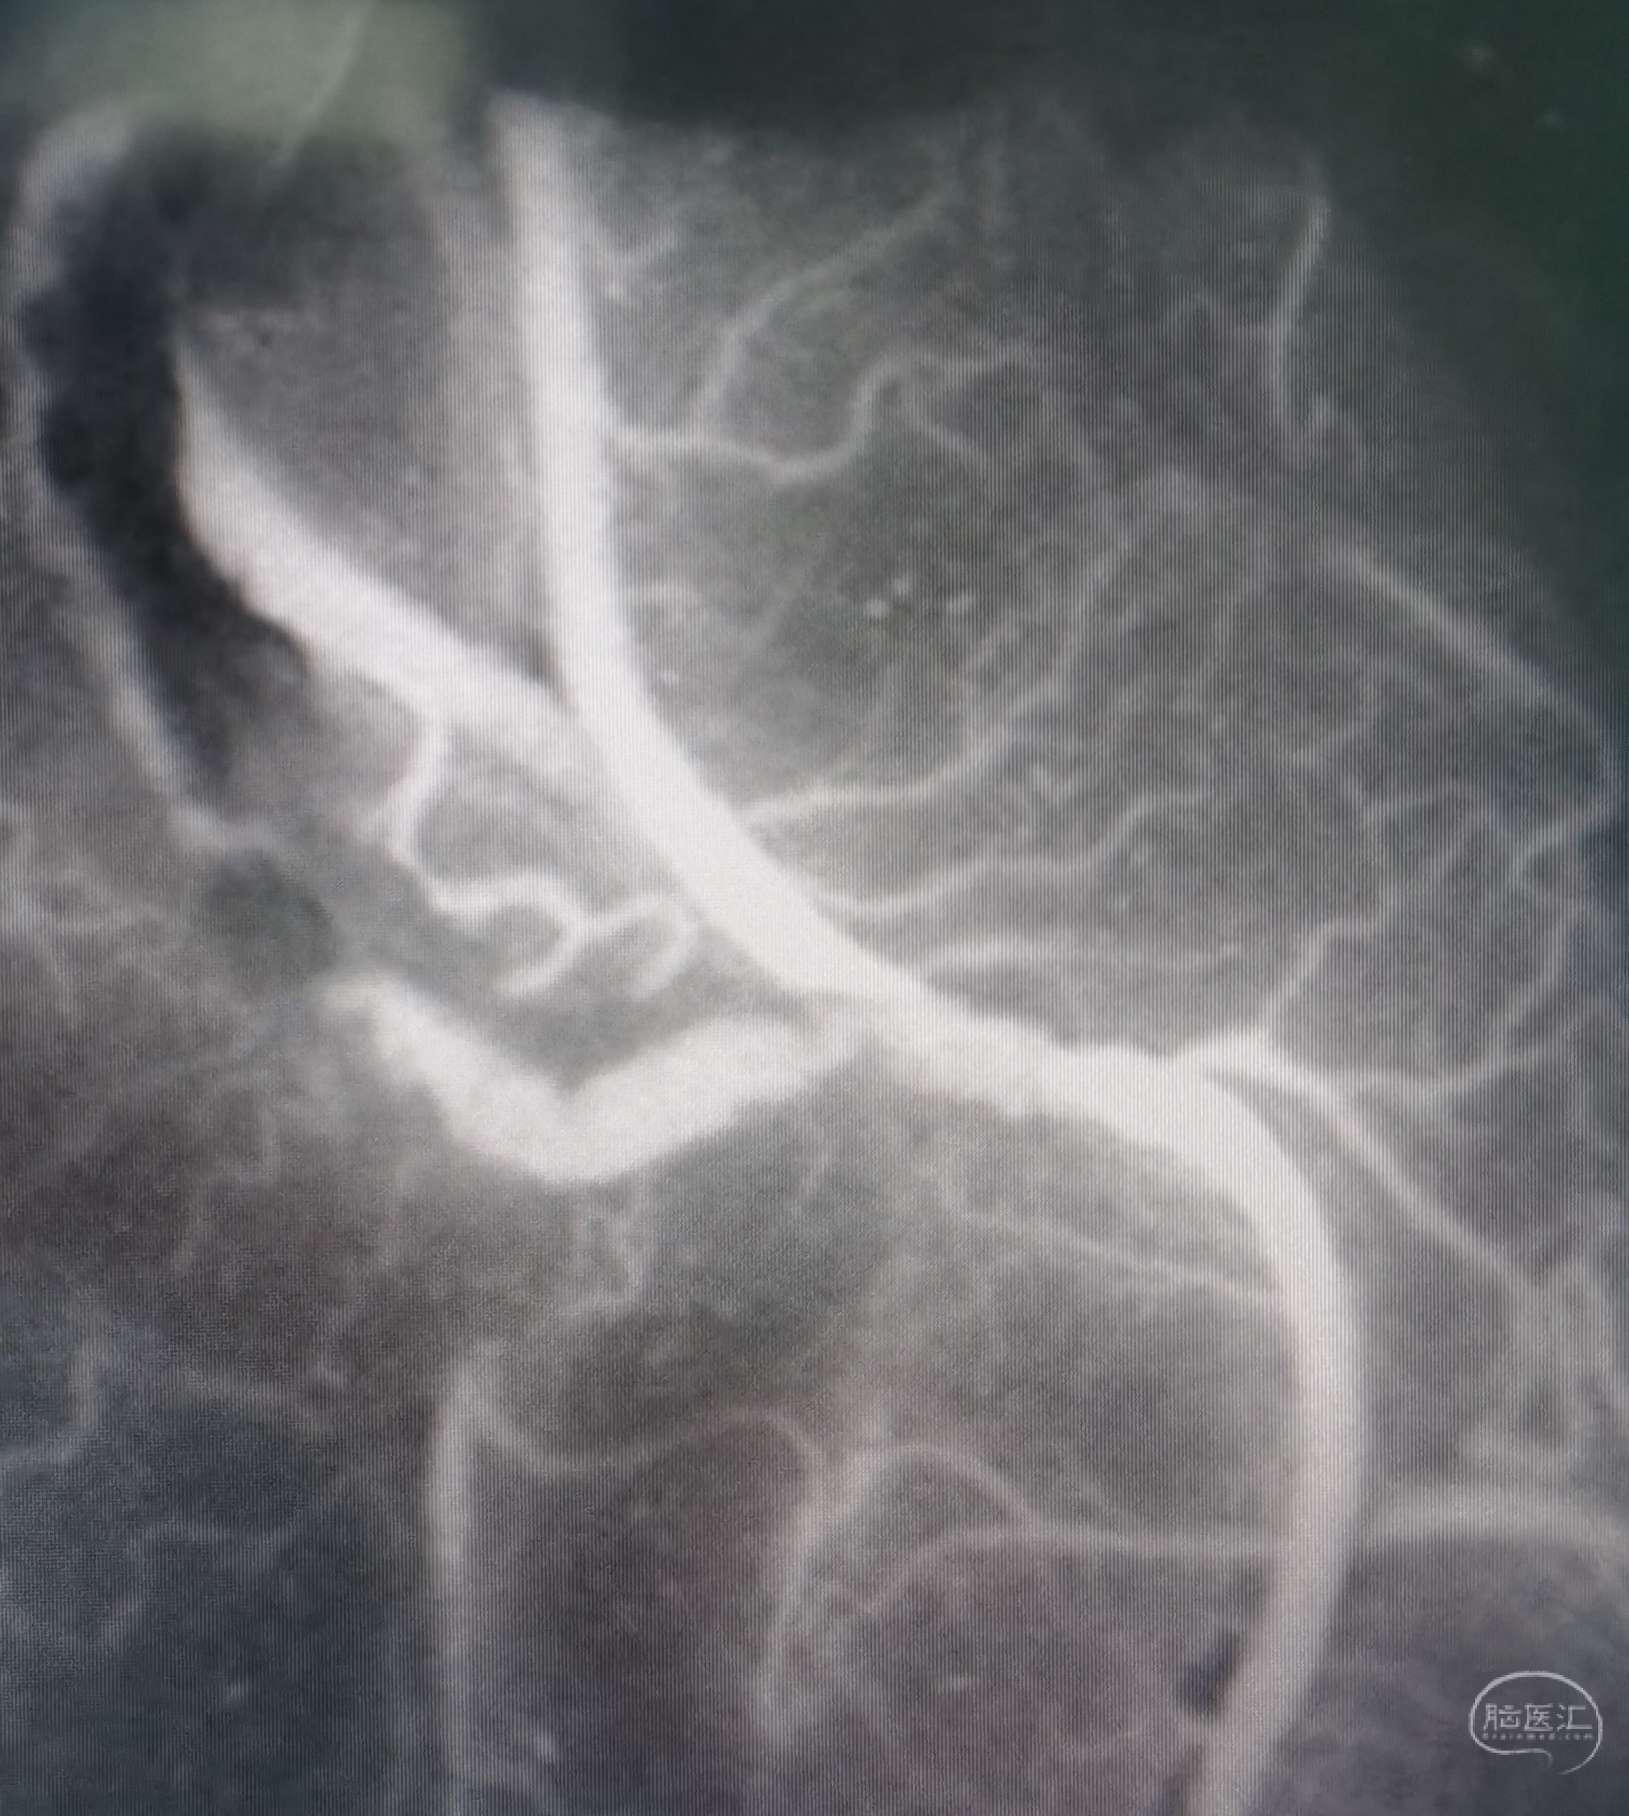

颞浅A-M4端侧吻合16针,荧光造影显示:吻合血管通畅。

颞浅A-M4端侧吻合14针,荧光造影显示:吻合血管通畅。